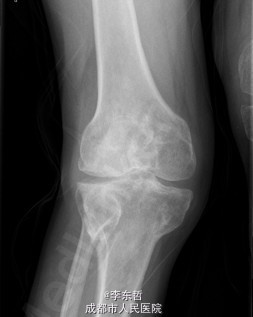

初步诊断:1、左侧股骨头坏死伴内收肌挛缩(Ficat IV期);2、右侧股骨头坏死(Ficat IV期);3、右膝骨关节炎伴外翻畸形;入院后积极完善术前检查及准备,择期行手术治疗。